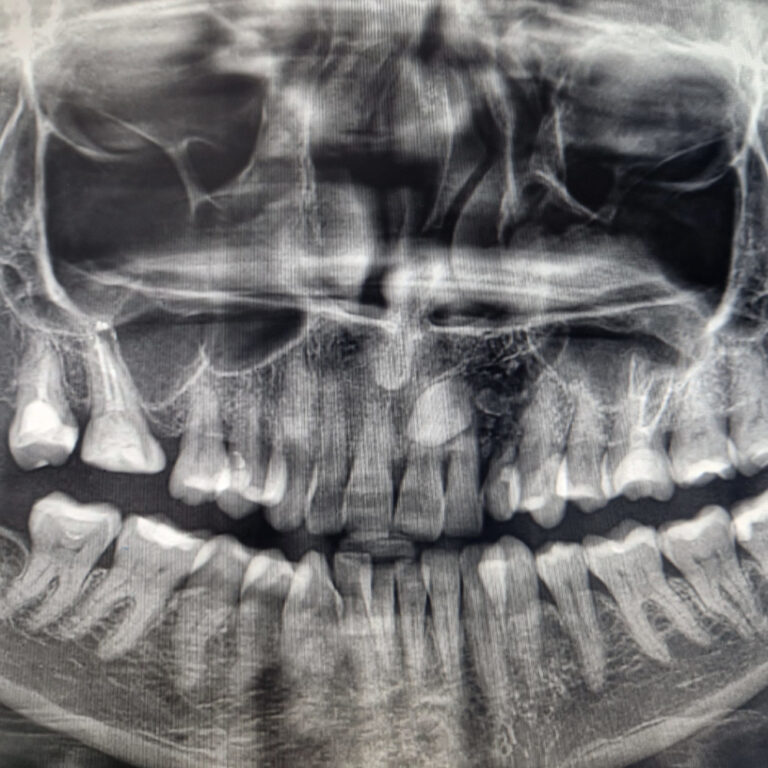

Implanty zygomatyczne

Przykłady implantologii

Zastosowanie implantoprotetyki w przypadku gdy klasyczna protetyka nie sprawdza się.